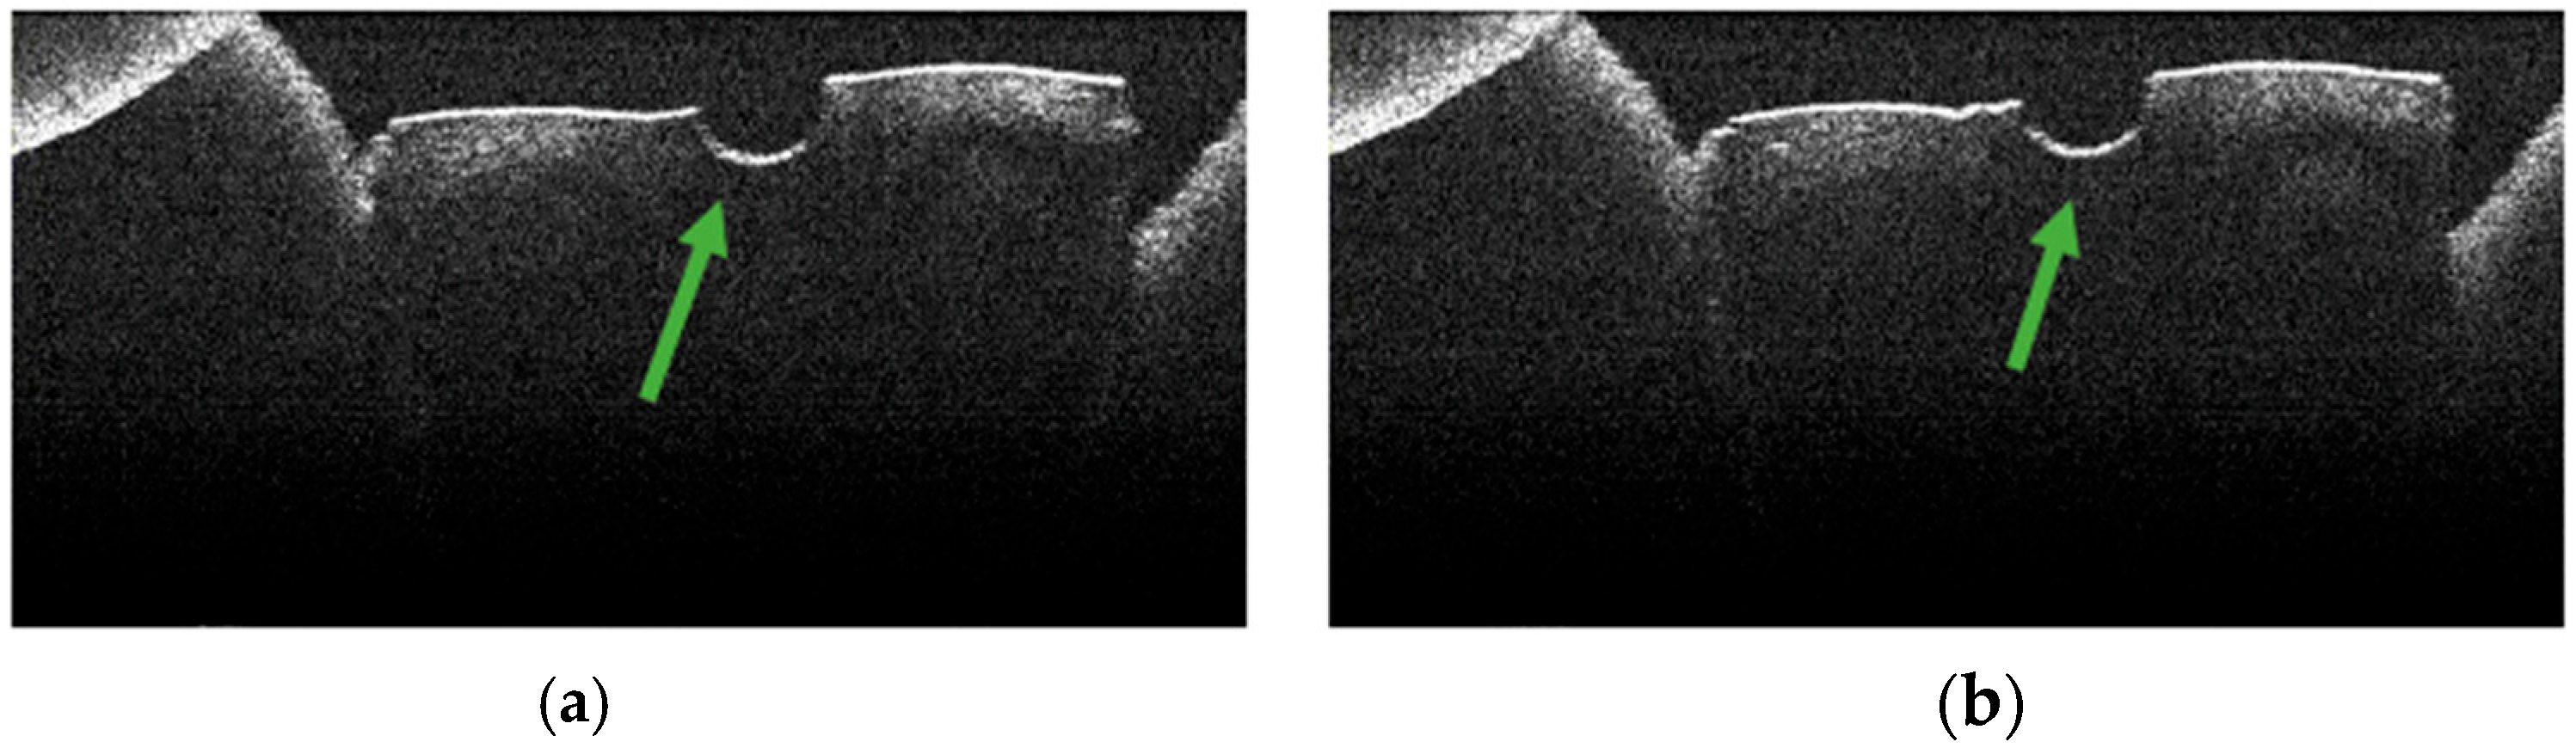

3.4. OCT Examination of Specimens from Group A

3.5. OCT Examination of Specimens from Group B